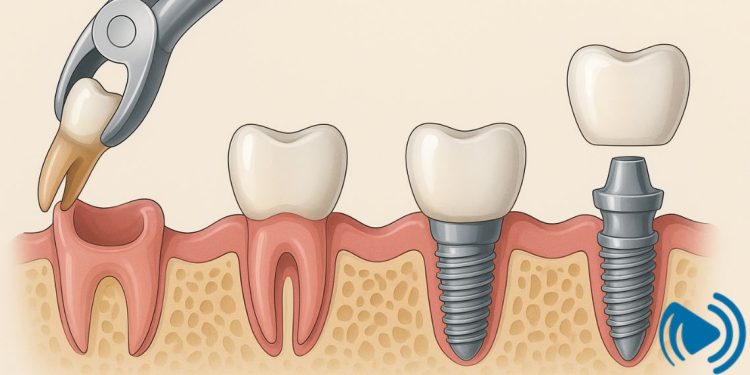

ایمپلنتگذاری یک عمل دقیق است که نیاز به شرایط خاص دارد. استخوان فک باید تراکم و کیفیت کافی داشته باشد تا پایه تیتانیومی ایمپلنت بتواند بهخوبی در آن جوش بخورد. اگر خیلی زود یا خیلی دیر اقدام شود، احتمال شکست ایمپلنت بالا میرود. به همین دلیل انتخاب زمان مناسب پس از کشیدن دندان اهمیت کلیدی دارد.

- ایمپلنت فوری: بلافاصله بعد از کشیدن دندان (همان روز یا ظرف ۴۸ ساعت). این روش تنها زمانی امکانپذیر است که عفونت وجود نداشته باشد، بافت لثه سالم باشد و تراکم استخوان کافی وجود داشته باشد.

- ایمپلنت زودهنگام: معمولاً ۲ تا ۸ هفته پس از کشیدن دندان. این روش زمانی مناسب است که نیاز به کمی ترمیم بافت نرم وجود داشته باشد اما استخوان فک هنوز تحلیل نشده باشد.

- ایمپلنت تأخیری: ۳ تا ۶ ماه پس از کشیدن دندان. این حالت زمانی توصیه میشود که عفونت وجود داشته یا استخوان نیاز به بازسازی داشته باشد. در این مدت، معمولاً پیوند استخوان یا درمانهای تکمیلی انجام میشود.

ایمپلنت فوری برای بسیاری از بیماران جذاب است چون در همان روز دندان جایگزین میشود. مزیت بزرگ آن جلوگیری از تحلیل استخوان و حفظ زیبایی لبخند است. اما عیب آن این است که در صورت وجود عفونت یا ضعف استخوان، احتمال شکست بالاتر است. بنابراین دندانپزشک تنها در موارد مناسب از این روش استفاده میکند. بنا به نوشته سایت implantandsedationexpert.com:

ایمپلنت فوری یا همان کاشت بلافاصله بعد از کشیدن دندان، روشی نوین است که با هدف کوتاهتر شدن زمان درمان و حفظ بافت نرم و سخت معرفی شده است. این روش میتواند نیاز به جراحیهای مکرر را کاهش دهد، مدت بیدندانی بیمار را کوتاه کند و حتی از تحلیل استخوان فک جلوگیری نماید. از نظر روانی هم بیماران با بازگشت سریع لبخند اعتمادبهنفس بیشتری پیدا میکنند. با وجود این مزایا، چالشهایی هم وجود دارد. دستیابی به پایداری اولیه ایمپلنت دشوارتر است، ترمیم بافتها همیشه قابلپیشبینی نیست و در بسیاری موارد نیاز به پیوند استخوان یا غشاء محافظ وجود دارد. به همین دلیل، ایمپلنت فوری تنها در شرایط خاص با استخوان و لثه سالم موفقیت بالایی دارد و در مواردی مثل عفونت فعال، بافت نازک یا تحلیل استخوان بهتر است روشهای زودهنگام یا تأخیری انتخاب شوند.

نقش پیوند استخوان در زمانبندی ایمپلنت

در بسیاری از بیماران پس از کشیدن دندان، استخوان فک کافی برای ایمپلنت وجود ندارد. در این موارد، دندانپزشک پیوند استخوان انجام میدهد و سپس چند ماه صبر میکند تا استخوان جدید با فک یکپارچه شود. پس از آن ایمپلنت با موفقیت بیشتری انجام خواهد شد.